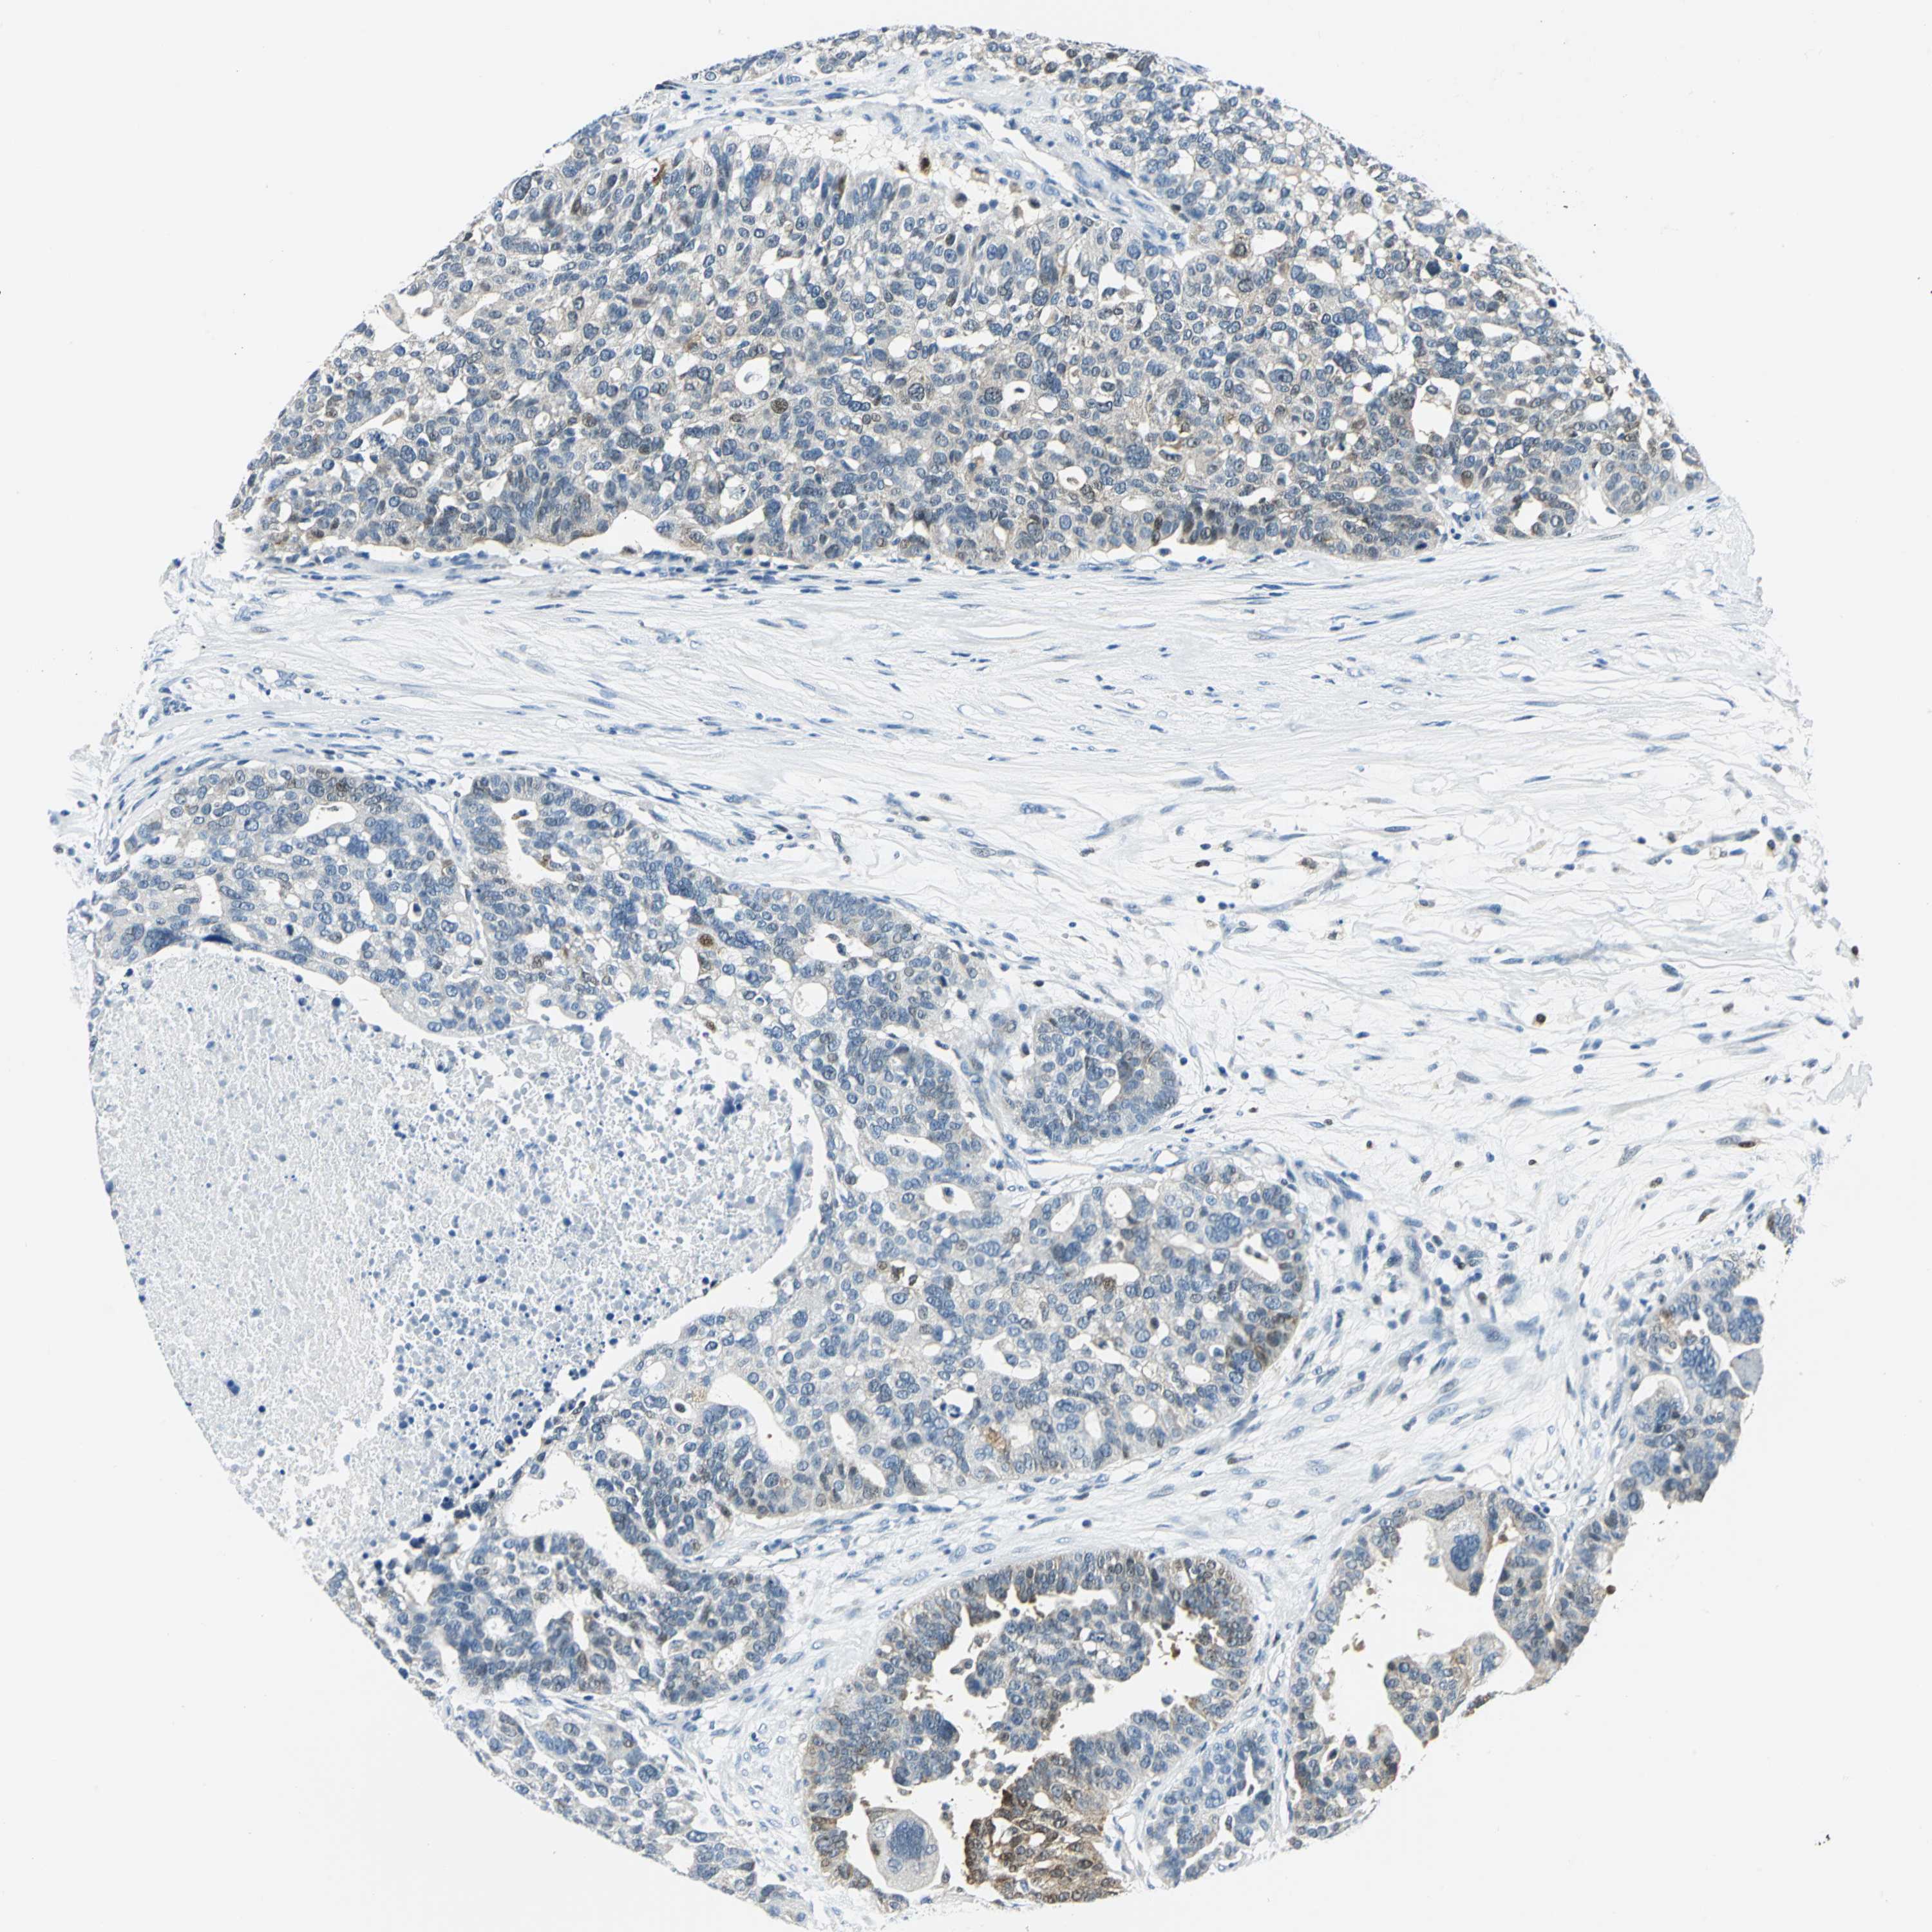

OVARIAN CANCER - Protein expressioni

A mouse-over function shows sample information and annotation data. Click on an image to view it in a full screen mode. Samples can be filtered based on level of antibody staining by selecting one or several of the following categories: high, medium, low and not detected. The assay and annotation is described here.

Note that samples used for immunohistochemistry by the Human Protein Atlas do not correspond to samples in the TCGA dataset.

Antibody stainingi

Antibody staining in the annotated cell types in the current human tissue is reported as not detected, low, medium, or high, based on conventional immunohistochemistry profiling in selected tissues. This score is based on the combination of the staining intensity and fraction of stained cells.

Each image is clickable and will lead to virtual microscopy that enables deeper exploration of all samples and also displays staining intensity scores, fraction scores and subcellular localization as well as patient and tissue information for each sample.

Antibody HPA019649

High

Medium

Low

Not detected

Carcinoma, endometroid